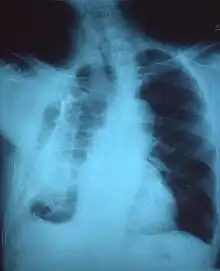

Extensive left-sided fibrothorax

Chest radiograph displaying inhomogeneous opacification of the left half of the chest that is fibrothorax

Autopsy specimen showing extensive pleural fibrosis